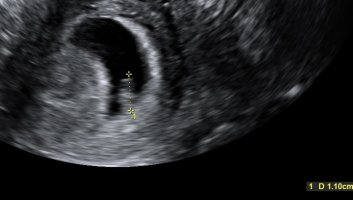

Mens vi venter på en skatt nr. 2 ❤️

6+5 TUL :Heartred

For en fantastisk følelse det er å kunne gå fra gynekologen etter å ha fått gode nyheter! Jeg har en liten skatt i magen med et bankende hjerte! :sad010

Alt så helt fint ut, og lengden stemte med hvor langt jeg er på vei. Dette var samme gynekologen som jeg har vært hos etter de to abortene, og det var så fint å merke at han var skikkelig glad på mine vegne. Han startet til og med timen 5 min. før tida så jeg skulle slippe å vente. Nå satte vi IVF-søknaden på pause, og det gjør meg optimistisk. Det betyr jo at gynekologen har skikkelig trua! Og endelig har jeg fått se at det er en konkret og fin årsak til kvalmen min, det hjelper. Jeg var SKIKKELIG nervøs før timen, og så for meg alle mulige scenarioer. Men tenk at JEG er gravid da dere?! Selv om den lille har vært i magen min i noen uker nå, så var det først nå at jeg virkelig føler at jeg er gravid, på ekte :Heartred